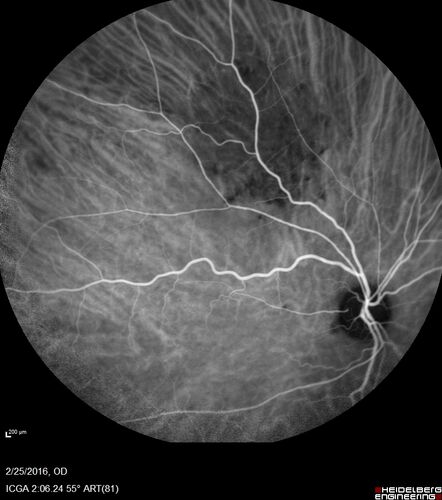

Amelanotic Choroidal Nevus - Multimodal Imaging

61 year old man with amelanotic choroidal nevus. Vision Normal - Stable over 4 years.